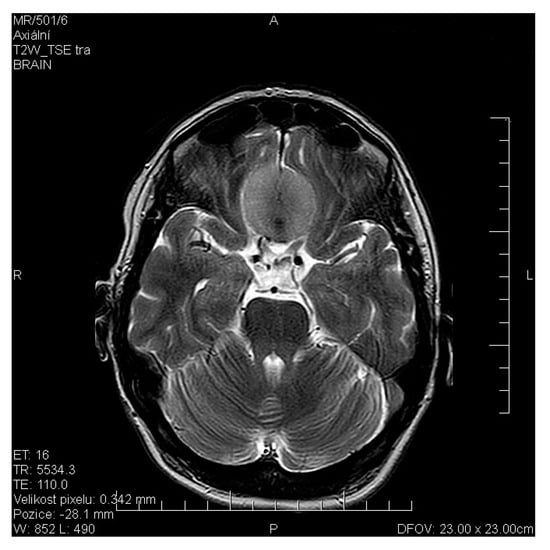

- Liu, J.; Pinto, J.M.; Yang, L.; Yao, L.; Miao, X.; Wei, Y. Evaluation of idiopathic olfactory loss with chemosensory event-related potentials and magnetic resonance imaging. Int. Forum. Allergy Rhinol. 2018, 8, 1315–1322. [Google Scholar] [CrossRef]

- Miao, X.; Yang, L.; Gu, H.; Ren, Y.; Chen, G.; Liu, J.; Wei, Y. Evaluation of post-traumatic anosmia with MRI and chemosensory ERPs. Eur. Arch. Otorhinolaryngol. 2015, 272, 1945–1953. [Google Scholar] [CrossRef]